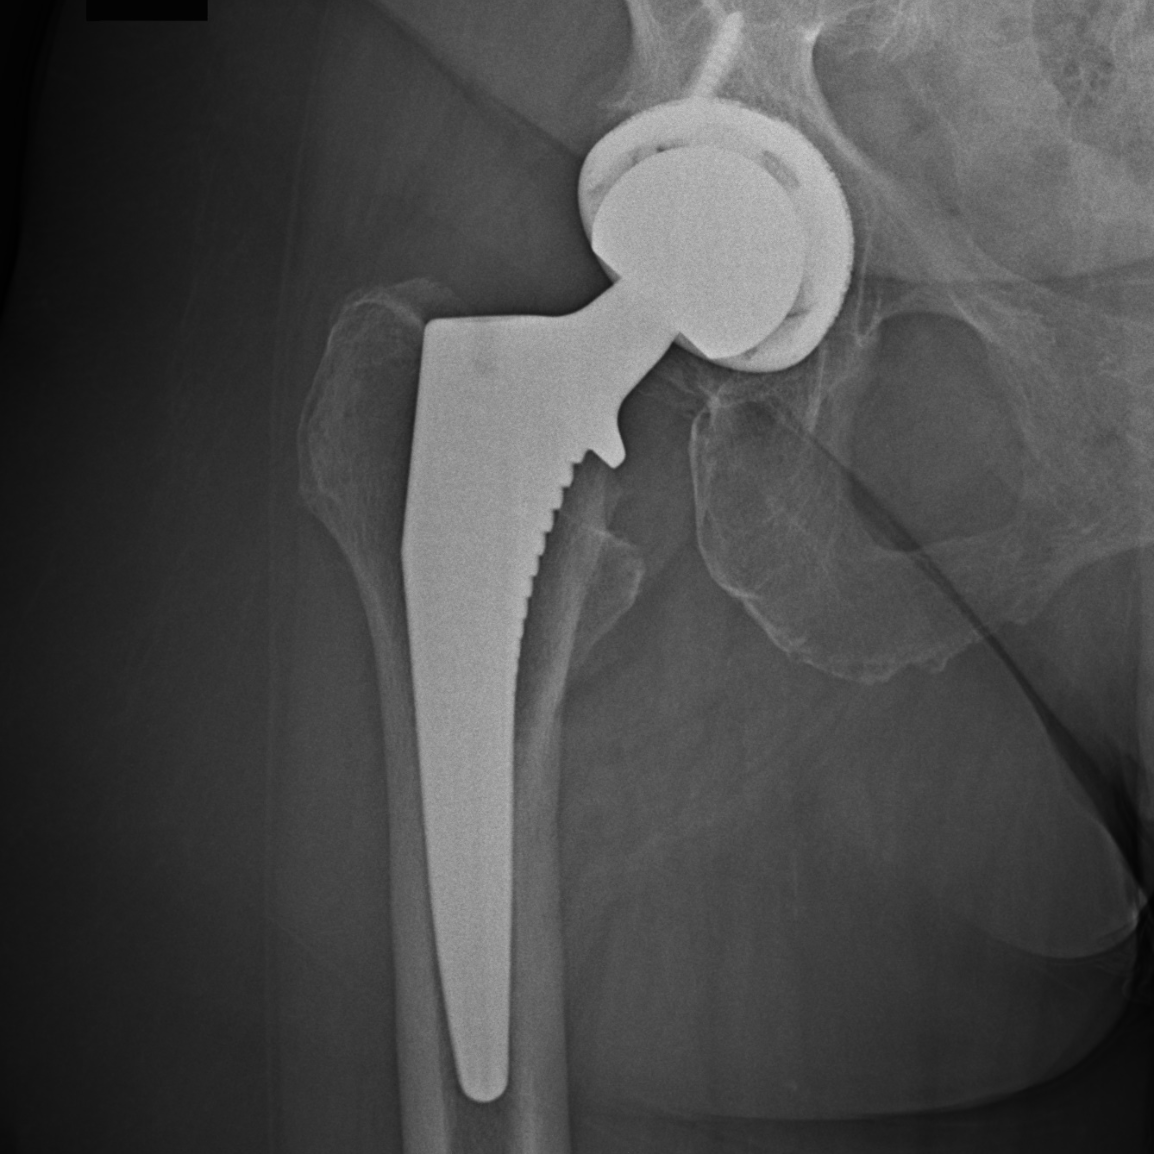

The x-ray performed during her visit Dr. Denehy demonstrated a shrinking joint space, indicative of end-stage arthritis of her right hip. A picture of her pre- and post-op x-ray is below: